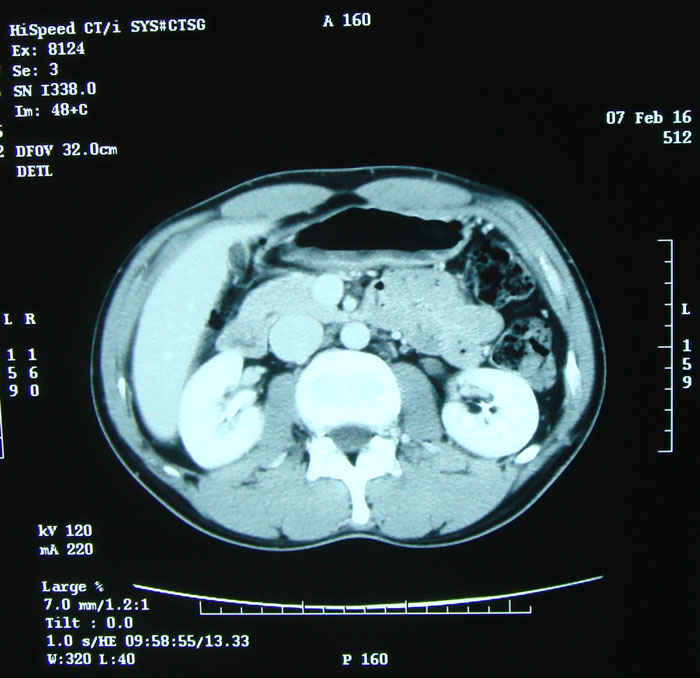

54.5kg/11.2% 2ヶ月ぶりのCT撮影。今回もくっきりな画像をと思い造影剤使用で。 造影剤の注射はすごくうまかった。痛みもほとんどなかったし針の跡も赤い点だけ。 その後、腫瘍マーカーのための採血。こちらも上手で痛みもなし。 今日は検査技師さんに恵まれたようだ。 いつもこうだといいんだけど・・・。 気になる結果は2/22。 といっても、蕎麦を食う、であるが。 ちょうど1クールの第一週が終わるころである。嘔吐ばかりしており食べることがままならない時期。この蕎麦、前職のころ毎日通っていた立ち食い。なぜか食べたくて仕方なかった。かけ220円;お好みでトッピング。安いがウマイ。 あの頃は他にも退院後にやりたいことを考えて現実逃避をしていた。ブログに書いてないことのひとつだった蕎麦は実現した。 まだまだやりたいことはある。次はなにが現実となるだろうか。楽しみだ。

退院後最初のCT撮影。1ヵ月半ぶり。